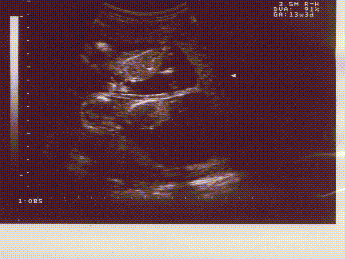

à 3 mois

TIC et TAC ....